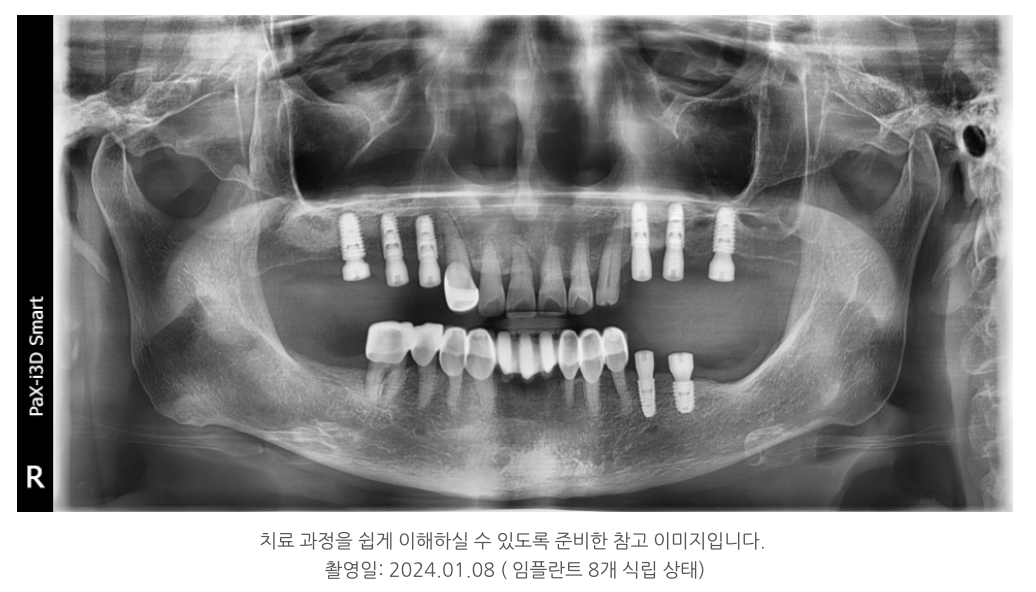

???? 실제 치료 사례 – 8개의 임플란트 식립

환자분은 양쪽 어금니가 모두 없던 상태였습니다.